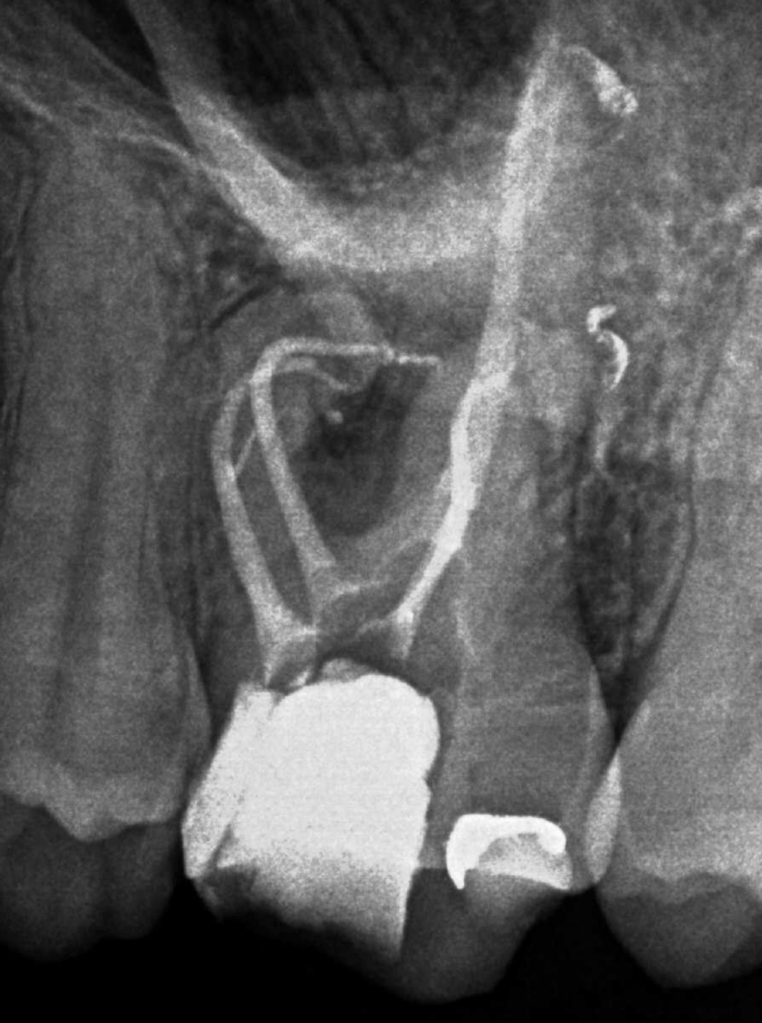

Vertical root fracture